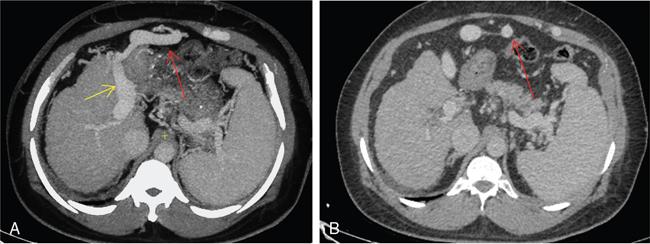

Shrinivas B. Desai, Ritu K. Kashikar, Aman Snehil, Ajay Jhaveri Cirrhosis is a late stage of irreversible scarring of the liver causing abnormality in liver structure and function. Multiple conditions and factors can cause repeated liver damage and scarring ultimately leading to cirrhosis. The most feared complication of liver cirrhosis is the development of hepatocellular carcinoma (HCC). Portal hypertension (PHT) is seen with a variety of conditions but cirrhosis happens to the most important cause. Imaging plays a vital role in noninvasive diagnosis and treatment planning of both cirrhosis and PHT. Liver imaging reporting and data system (LI-RADS) is a standardized reporting system assigning an observation risk of representing HCC. This chapter focuses on discussing aetiologies and imaging of PHT with a lucid review of L1-RADS 2018 version. The portal blood circulation is a unique circulatory circuit as it connects two capillary beds between the liver parenchyma at one end and the gastrointestinal tract and splenic parenchyma at the other end. The portal system ramifies in the liver and ultimately ends in the hepatic sinusoids from where the blood ultimately drains into the inferior vena cava (IVC). The portal vein (PV) originates from the capillary beds in the stomach, intestine and the spleen. The main PV is formed behind the neck of the pancreas by the confluence of the superior mesenteric vein (SMV) and splenic vein. It continues to the porta hepatis where it bifurcates into the left and right branches as it carries nutrient rich but oxygen poor blood to the liver (Fig. 9.9.1). The PV makes up for 75%–80% of the liver’s blood supply while the hepatic artery which arises from the celiac trunk makes up for the remaining 25%. A pathological increase in the portal venous pressure is referred to as PHT. PHT is most often a sequel of chronic parenchymal liver disease and leads to major life-threatening complications due to bleeding from the collateral circulation (most commonly oesophageal varices). Direct measurement of portal pressure (PP) is invasive and often not feasible in most patients and thus imaging plays an important role in the diagnosis of PHT and its complications. The normal portal venous pressure ranges between 5 and 10 mmHg, which is the equivalent of 7–14 cm H2O. The normal hepatic venous pressure gradient (HVPG) is the pressure gradient between the PV and the IVC, is typically 1–5 mmHg. Presence of PHT is indicated by a wedged hepatic venous pressure of more than 5 mmHg. Other definitions include a splenic pressure of more than 15 mmHg or an intraoperative PP of greater than 30 cm H2O. The complications of PHT are seen when HVPG is greater than 10 mmHg and hence this value defines clinically significant PHT. Variceal bleeding is seen with a pressure greater than 12 mmHg. In ideal conditions, the portal circuit is a high flow, low resistance circuit as it has to allow substantial flow rates of 700–1000 mL/min to the hepatic parenchyma from the gastrointestinal tract. Anatomical changes in the organization of the hepatic lobule can result in rise in the portal resistance. These can occur in the form of collagen deposition in the space of Disse, fibrotic scars formed due to regenerative nodule (RN) formation, loss of normal elasticity of the endothelium and distal venous thrombosis. Changes in splanchnic haemodynamics due to factors that increase splanchnic blood flow and increase in intrahepatic vascular resistance due to transformation of stellate cells into myofibroblasts also contribute to the increase in PP gradient. In Western countries, alcoholic cirrhosis and viral cirrhosis are the leading causes of PHT and oesophageal varices. The viral causes form majority of cases leading to cirrhosis and PHT in the Far East and Middle Eastern countries while Schistosomiasis remains an important cause in the African countries. Worldwide, nonalcoholic steatohepatitis (NASH) and hepatitis C are the emerging causes of chronic liver disease (CLD) and PHT. PHT can be classified as cirrhotic and noncirrhotic depending on whether it is associated with cirrhosis or not. This distinction is important as noncirrhotic causes like PV thrombosis are at high risk of development of bleeding but tend to have a better chance of surviving a variceal bleed than a patient with decompensated alcoholic cirrhosis due to preserved hepatic synthetic functions in the former. PHT can also be classified on the basis of the location of the pathology into prehepatic, hepatic and posthepatic causes. Hepatic causes can further be divided into presinusoidal, sinusoidal and postsinusoidal. The causes of portal hypertension have been denoted in Table 9.9.1. The direct measurement of the PP by measuring the HVPG is invasive, expensive not readily available in all patients. Thus, imaging plays an important role in the diagnosis of PHT. Various modalities are used for the imaging diagnosis of PHT. Ultrasonography (USG) and Doppler evaluation have the advantage of being inexpensive, readily available and bedside modality (Table 9.9.2). The role of ultrasound and Doppler in imaging of PHT is to: Grey scale imaging is useful in evaluating the splenoportal anatomy. The evaluation should begin with the liver morphology. Signs of cirrhosis like nodularity of the liver surface with relative atrophy of the right lobe and prominence of the left lobe and caudate should be looked for. Hepatic echotexture appears coarse and more echogenic (Table 9.9.3). Increase in portal venous diameter is a sign of PHT (Fig. 9.9.2). Portal venous diameter of more than 13 or 15 mm has low sensitivity for diagnosing PHT of only 40%–12.5%, respectively. Absolute measurement of the portal diameter as a sign of PHT is also fallacious as in presence of collateral circulation or hepatofugal flow; there may actually be a decrease in the PV diameter. Therefore, a more accurate sign is respiratory variation of PV diameter. An increase in PV diameter of less than 20% with deep inspiration has been reported to indicate PHT with a sensitivity of 80% and specificity of 100%. This has been reported to be an accurate indicator of cirrhosis. Hepatic vein straightness, uniformity of vein wall echogenicity and visualization of at least 1 cm segment of the hepatic vein are the parameters used for evaluation. Splenomegaly is defined as bipolar splenic diameter of greater than 12 cm or largest splenic cross-sectional area passing through the hilum of greater than 45 cm2, and occurs secondary to PHT (Fig. 9.9.3). A total of 65%–80% patients with cirrhosis have splenomegaly on ultrasound. Patients with cirrhosis due to viral hepatitis and primary biliary cirrhosis show splenomegaly more frequently than those with alcoholic cirrhosis. This is an accurate sign of PHT. USG is extremely sensitive with respect to detecting subclinical ascites. Perihepatic space is the most usual site of visualization of minimal ascites. In normal subjects, this ratio is approximately 0.07 and a value above 0.1 suggests the diagnosis of PHT with a 95% sensitivity and specificity. The normal spectral waveform of the hepatic artery is a low resistance flow pattern with forward flow in diastole and a resistivity index in the range of 0.5–0.7. In PHT, the resistivity index of the hepatic artery increases with high resistance flow pattern due to increased peripheral vascular resistance. Resistance index (RI) > 0.78 in the intrahepatic branches of the hepatic artery has been reported to have a sensitivity of 50% and a specificity of 100% for the detection of PHT (Fig. 9.9.11). Pulsatility index (PI) > 1.05 suggests severe PHT with a sensitivity of 86% and specificity of 88% (Fig. 9.9.11). Patency of hepatic veins should be evaluated to rule out Budd–Chiari syndrome as a cause of PHT. The normal hepatic venous waveform (HVW) reflects right atrial activity and this results in a triphasic waveform with one positive and two negative waves. In PHT, this waveform becomes monophasic or biphasic. A monophasic HVW has a sensitivity and specificity of 74% and 95%, respectively, in the diagnosis of severe PHT (Fig. 9.9.12). Dilatation of the splanchnic veins – the SMV and the splenic vein – more than 11 mm are suggestive of PHT with a sensitivity and specificity of 72% and 100%, respectively. A reduction in the respiratory variation of the splenic vein and SMV to less than 40% had a sensitivity and specificity of 79.7% and 100%, respectively, for the diagnosis of PHT (Fig. 9.9.13). The splenic artery reveals an increase in the resistivity index and an RI of >0.63 and a PI of >1 have a sensitivity and specificity of 84.6% and 70.4% for the diagnosis of PHT. Presence of portosystemic collaterals like patent paraumbilical vein, dilated left gastric and short gastric veins are 100% specific sign for PHT (Figs. 9.9.14–9.9.16). Recanalization of the paraumbilical vein, known as the Cruveilhier–Baumgarten syndrome is observed in 43% of patients with PHT, and this is the easiest collateral to assess during the US examination. Various portosystemic collaterals that occur in PHT have been discussed in details in subsection on CT findings in PHT. No Doppler parameter is considered reliable enough to measure PP with sufficient accuracy for use in clinical practice. Oesophageal varices are often present in patients with portosystemic collaterals. Appearance or increase in number of collaterals along with splenomegaly has a high association with variceal formation and growth. USG helps in diagnosis of prehepatic causes like portal stenosis or thrombosis by demonstrating the patency and morphology of the splenoportal system. Arteriovenous fistulae and tumours causing vascular thrombosis as aetiology can be readily detected. USG helps in diagnosis of features of cirrhosis and thus helps differentiate noncirrhotic causes of PHT. USG allows diagnosis of fatty liver disease, which is an emerging cause of cirrhosis. Among the posthepatic causes, USG aids in establishing the diagnosis of Budd–Chiari syndrome by demonstrating the patency and morphology of the IVC and hepatic veins. Owing to the inability of CT to detect flow direction, portal flow rates or pressure gradients, CT is not the primary modality in diagnosis of PHT. Similar to USG dilatation of portosystemic system is a feature of PHT (Fig. 9.9.17). Changes in cirrhosis if present can be seen in the form of surface nodularity, nodules and fibrous septae. CT plays an important role in diagnosis of portal venous thrombosis and evaluating its extent. An acute thrombus is seen as a hypodense filling defect in the vessel causing distension of the venous lumen. Surrounding fat stranding can be seen. A chronic thrombus appears as an eccentric filling defect usually along the wall and is often associated with decrease in vessel diameter. Calcification may be seen in chronic thrombi. Multidetector computed tomography (MDCT) is a useful tool to evaluate portosystemic collateral circulation and recognize complications of PHT. 3D angiography can help understand portal venous and complex variceal anatomy and plan treatment. The various portosystemic collaterals are discussed below. They can be classified into those draining into superior vena cava (SVC) and those draining into the IVC. Magnetic resonance imaging (MRI) is a noninvasive modality used in the evaluation of PHT without the use of ionising radiation. It provides evaluation of parenchymal abnormalities, collaterals and characterization of tumours (Fig. 9.9.28). Spin echo sequences allow characterization of liver masses and liver parenchyma. Loss of flow void allows for detection of thrombosis. Time-of-flight (TOF) angiography is useful in assessing the portal venous system and allows for successful detection of PV thrombosis. The disadvantages of TOF are motion artefacts caused by breathing, long acquisition times and incomplete coverage of the portal venous system. Novel imaging techniques include phase contrast, T1 mapping and magnetic resonance elastography (MRE). The advantage of phase contrast over TOF imaging is that phase contrast imaging acquires information regarding the flow direction in addition to the information regarding the flow velocity. On-phase contrast images signal within vessel is hyperintense when flow is cranial and hypointense when flow is caudal. Look-Locker imaging technique using gradient echo (GRE) MRI sequences with inversion recovery pulse is used to quantify fibrosis by measuring precontrast T1 relaxation times. Interventions in PHT can be aimed at diagnosis or more commonly at management of complications of PHT. HVPG measurement, which is the gold standard for the diagnosis of PHT, can be achieved through cannulation of the PV. Transjugular hepatic biopsy is another diagnostic invasive technique that also allows indirect measurement of PP. Disadvantages include deterioration of hepatic function caused by diversion of portal venous blood flow and shunt dysfunction. TIPSS is contraindicated in patients with congestive heart failure, severe pulmonary hypertension, severe tricuspid regurgitation and hepatic failure. In this technique, a catheter is advanced from the femoral vein into the outlet of the gastrorenal, usually in the region of the left renal vein. The shunt is then occluded with a balloon and sclerosant is injected retrograde to occlude the gastric varices. Histological development of RNs surrounded by fibrous septae in response to chronic liver injury, progressing PHT and end-stage liver disease is termed as cirrhosis. Although initially considered an end-stage phenomenon in CLD, recent evidence suggests that the histological fibrosis can be reversible in early stages with the initiation of specific therapies, for example, in viral cirrhosis with the initiation of antiviral therapy. The one-year mortality rate in cirrhosis varies widely from 1% to 57% depending on the occurrence of complications. Cirrhosis can have a wide variety of causes ranging from congenital to acquired and infectious to noninfectious. It is also a major aetiologic risk factor for the development of HCC. Imaging plays an important role in aetiologic diagnosis of this diverse entity as well as in the diagnosis and management of its complication and surveillance for oncological transformation.